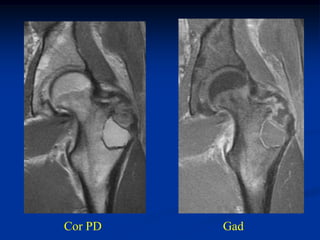

Cor PD   Gad

Axial T-1               T-2

T-2   Gad